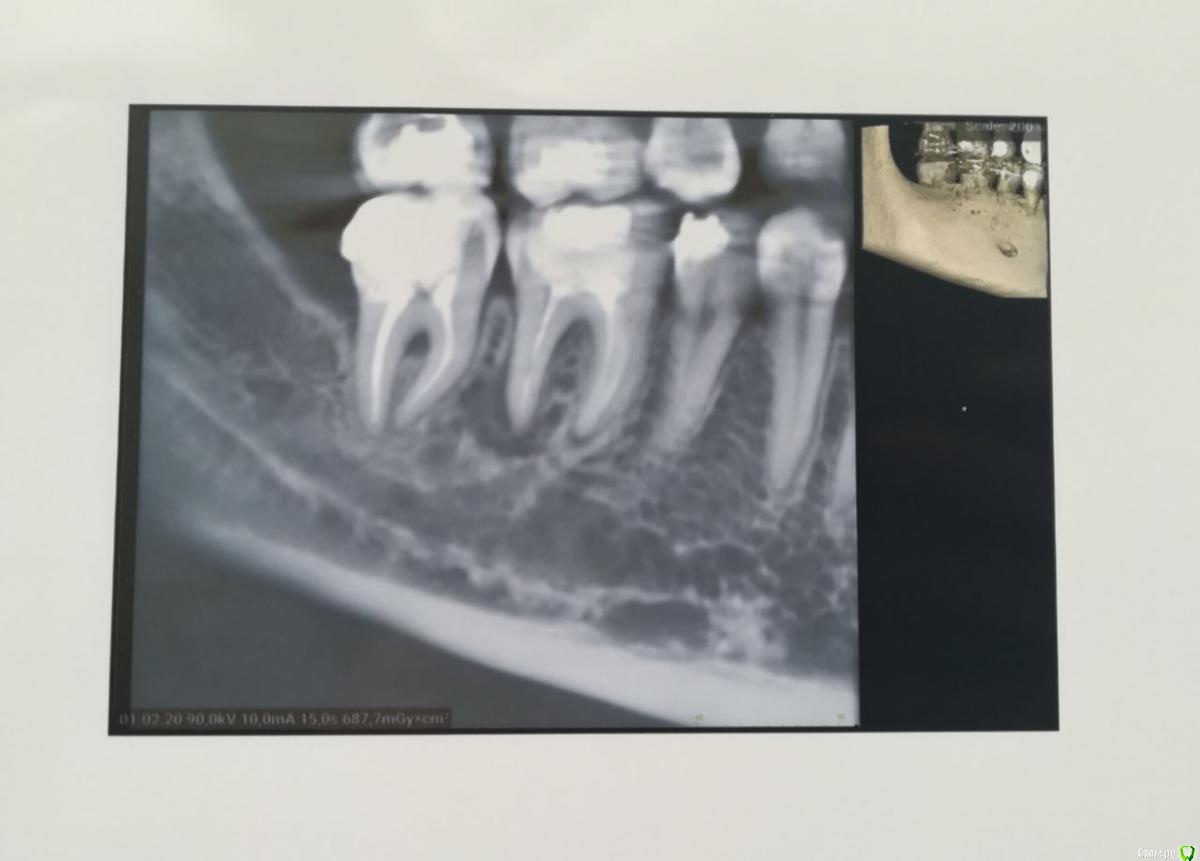

Tansky Опубликовано 18 марта, 2020 Автор Поделиться Опубликовано 18 марта, 2020 снимки - пара отпг до орто и актуальная, от 17.03.2020пара кт, в области интереса 3.6 и 4.7, разные снимки Ссылка на комментарий

Tansky Опубликовано 18 марта, 2020 Автор Поделиться Опубликовано 18 марта, 2020 разные проекции и описание заключения. прицельные rg есть еще по тому же зубу разных времен, но это надо искать дома и фоткать с негатоскопа или днем на свет Ссылка на комментарий